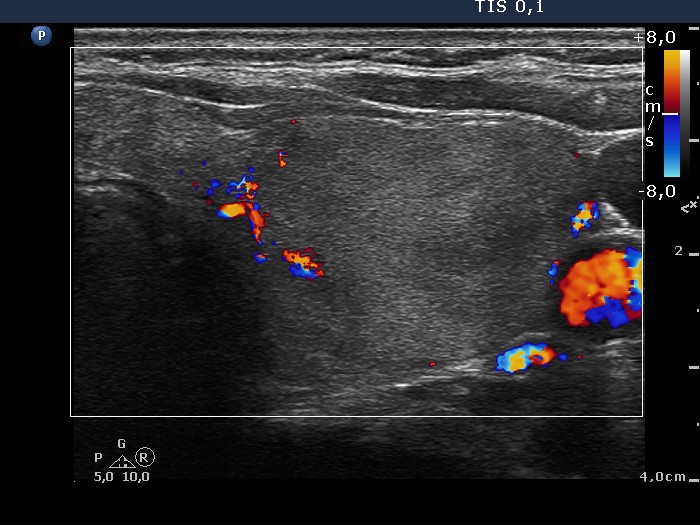

Left lobe, transverse scan, color Doppler mode. The nodule presents signs of perinodular blood flow.